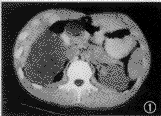

B超:右肾下极见一9.8 cm×8.4 cm×6.9 cm 的中等回声区,其内回声均匀,边界清楚,包膜完整,肾盂部分受侵。彩色多普勒超声显像(CDFI):肿物内部见点状血流。诊断:右肾下极实性占位,恶性肿瘤可能性大。CT检查:右肾中下极可见一巨大椭圆形肿块,边缘光滑,大小约10 cm×8 cm×8 cm ,其内密度较均匀,平扫时CT值为19~26 HU(图1),增强后为45~65 HU(图2),肾实质平扫时的CT值41.5 HU,增强后为145 HU。右肾后部实质弧形受压,肾盂变扁,向后内侧移位,肿块压迫下腔静脉向外移位。诊断:右肾中下极实性占位病变,肿瘤可能性大。

图1 右肾中下极可见一巨大椭圆形肿块,边缘光滑,密度较均匀